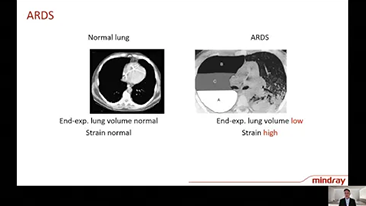

??cz?c w jednym urz?dzeniu wysokoprzep?ywow? terapi? tlenow?, wentylacj? nieinwazyjn? i wentylacj? inwazyjn?, respiratory typu 3 w 1 z serii SV zapewniaj? stabilne dzia?anie, wszechstronne funkcje i ?atwo?? u?ytkowania. Unikalne funkcje ochrony p?uc i wiele narz?dzi wspomagaj?cych podejmowanie decyzji zosta?y opracowane w celu zmniejszenia ryzyka zaka?eń krzy?owych i u?atwienia opiekunom wykonywania codziennych obowi?zków.